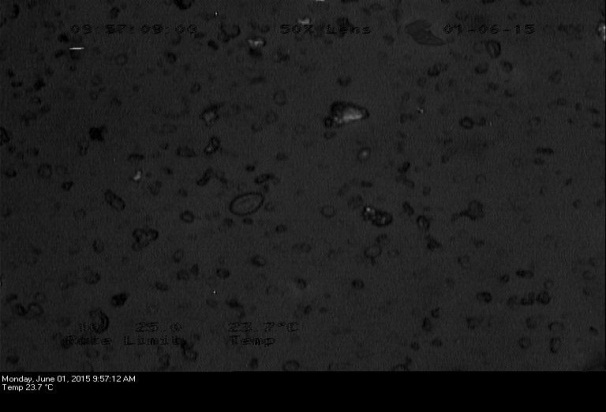

Optical and polarized microscopy

Each sample (<0.1 mg) was mounted on a glass slide with a brush, covered with silicone oil and a coverslip and was observed under the microscope (Lecia DMLP, Germany). Light intensity was adjusted and observations were done under normal and polarized light (by engaging the polarizer). Birefringence patterns were observed at a high-resolution scale and images were acquired.

Fig. 2: Optical micrographs of (a1) FB (b1) Spray-dried FB (c1) HPMC physical mixture (d1) HPMC solid dispersion (e1) HPMCAS physical mixture (f1) HPMCAS solid dispersion. Polarized micrographs of (a2) FB (b2) Spray-dried FB (c2) HPMC physical mixture (d2) HPMC solid dispersion (e2) HPMCAS physical mixture (f2) HPMCAS solid dispersion

Optical and polarized microscopy was done to observe the birefringence pattern. Fig. 2 showed optical and polarized micrographs of the drug, polymeric carriers, physical mixtures and solid dispersions. Presence of birefringence confirms the presence of crystallinity in the samples. However, loss of crystallinity was observed in prepared physical mixtures and solid dispersions by uniform dispersion of the drug in molecular matrix. This phenomenon suggested effective encapsulation of FB into the hydrophilic matrix of HPMC and HPMCAS with no evidence of FB crystals on the surface.